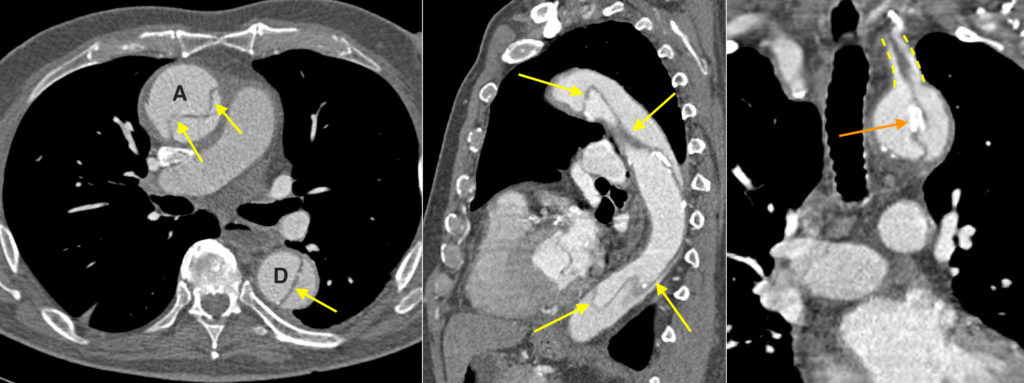

Figure 4 CTA Showing A Type A Aortic Dissection Extending Along The

Thoracic Aortic Dissection CT Radiology At St Vincent s University

Computed Tomography With Contrast Enhancement In A Patient With Acute